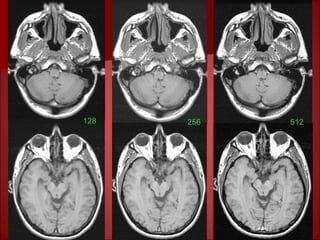

Spatial Resolution

Factors affecting spatial resolution:

• RBW: as RBW widens, spatial resolution increases as the

data building the image ( signal frequencies) increases.

• Matrix (Phase & Frequency dimensions): as

matrix increases, PVA decreases increasing spatial

resolution.

• Thickness (Slice dimension): as thickness

decreases, PVA decreases increasing the spatial resolution.

• FOV: as FOV decreases, PVA decreases, increasing the

128 256 512